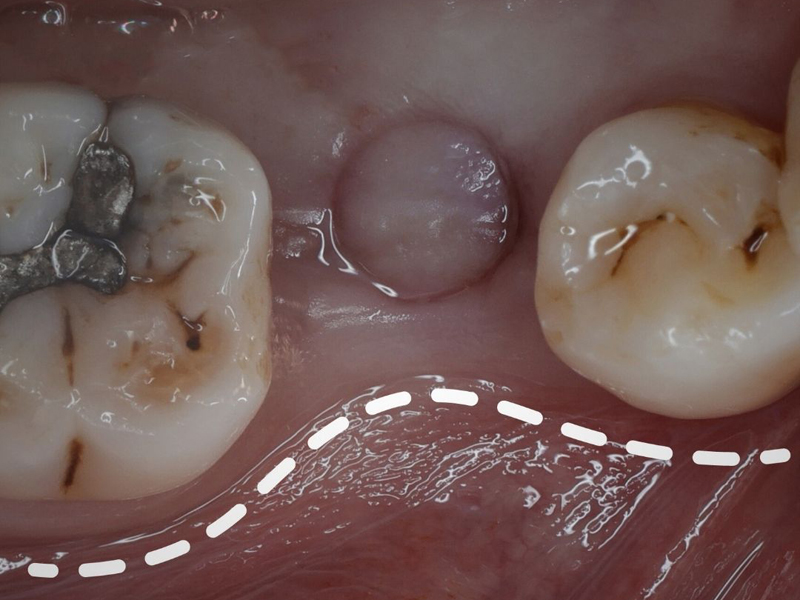

高效補骨 首頁 美麗見證 高效補骨 補骨不可怕,植牙失敗才可怕! 兆品美學牙醫用案例告訴你!植牙就像蓋房子,地基穩不穩固很重要 More 為什麼需要補骨,不能直接植牙呢? 造成骨量不夠的原因通常是缺牙時間過長、牙周病、年齡老化⋯⋯ More «1»